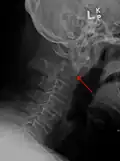

Fractures

A fracture of both pedicles of the axis is termed a Hangman's fracture.

Fractures of the dens are classified into three categories according to the Anderson Alonso system:

• Type I fracture - Extends through the tip of the dens. This type is usually stable.

• Type II fracture - Extends through the base of the dens. It is the most commonly encountered fracture for this region of the axis. This type is unstable and has a high rate of non-union.

• Type III fracture - Extends through the vertebral body of the axis. This type can be stable or unstable and may require surgery.[1]